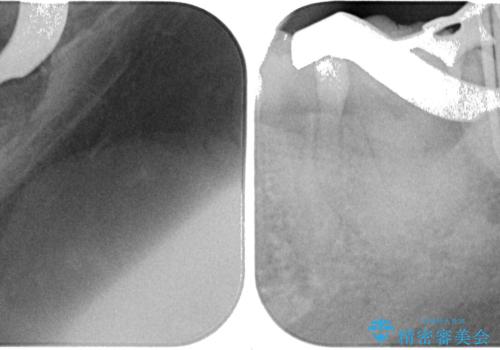

奥に埋もれている親知らずが原因でむし歯になり、以前に根管治療を行った歯が痛みの原因であり、再度根管治療が必要な状態でした。

歯根先端付近の歯槽骨が溶けてるレントゲン像が認められましたが、治療から半年後のレントゲン写真では、消退している様子が認められました。